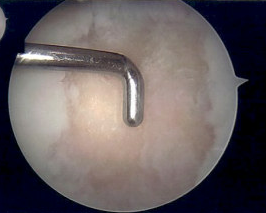

Microfracture

Microfracture of trochlea chondral defect